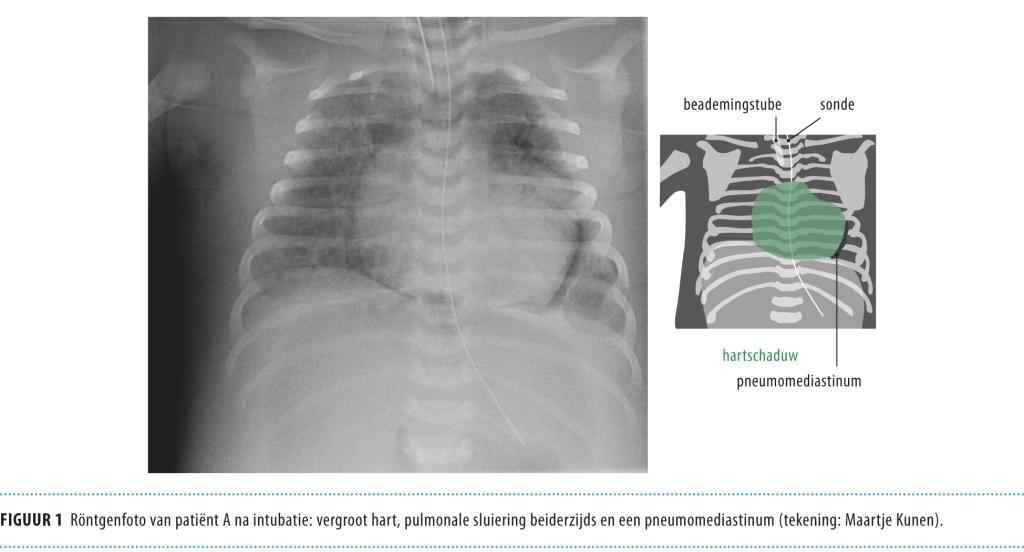

Op onze afdeling Kinderintensivecare werden 2 ernstig zieke mannelijke pasgeborenen opgenomen in het voorjaar en de zomer van 2008. Initieel waren de klachten bij beiden koorts, grauw-zien en slechter drinken. Bij lichamelijk onderzoek vielen tachycardie, vertraagde capillaire vulling en een vergrote lever op. Binnen enkele uren trad bij de patiënten circulatoir en respiratoir falen op. Op de thoraxröntgenfoto was een vergroot hart zichtbaar; echocardiografie toonde een sterk afgenomen pompfunctie van beide hartkamers. De diagnose ‘myocarditis door coxsackie B3-virus’ werd gesteld nadat dit virus was aangetoond in het serum en de feces. De ene zuigeling had tot bij het laatste follow-uponderzoek persisterende ernstige pompfunctiestoornissen van het hart, de andere overleed. Coxsackie B3-virus is een non-polio-enterovirus dat over het algemeen milde ziekteverschijnselen veroorzaakt, maar is ook geassocieerd met myocarditis en fulminant verlopende neonatale infecties. Bij pasgeborenen met geringe, algemene ziekteverschijnselen dient men bedacht te zijn op progressie naar circulatoir falen, zeker als de moeder in de perinatale periode ook verschijnselen heeft van een virale infectie. Snelle onderkenning van hartfalen en diagnostisch onderzoek naar cardiotrope virussen zijn aangewezen, want het gaat om een ziekte met een grote morbiditeit en sterfte.